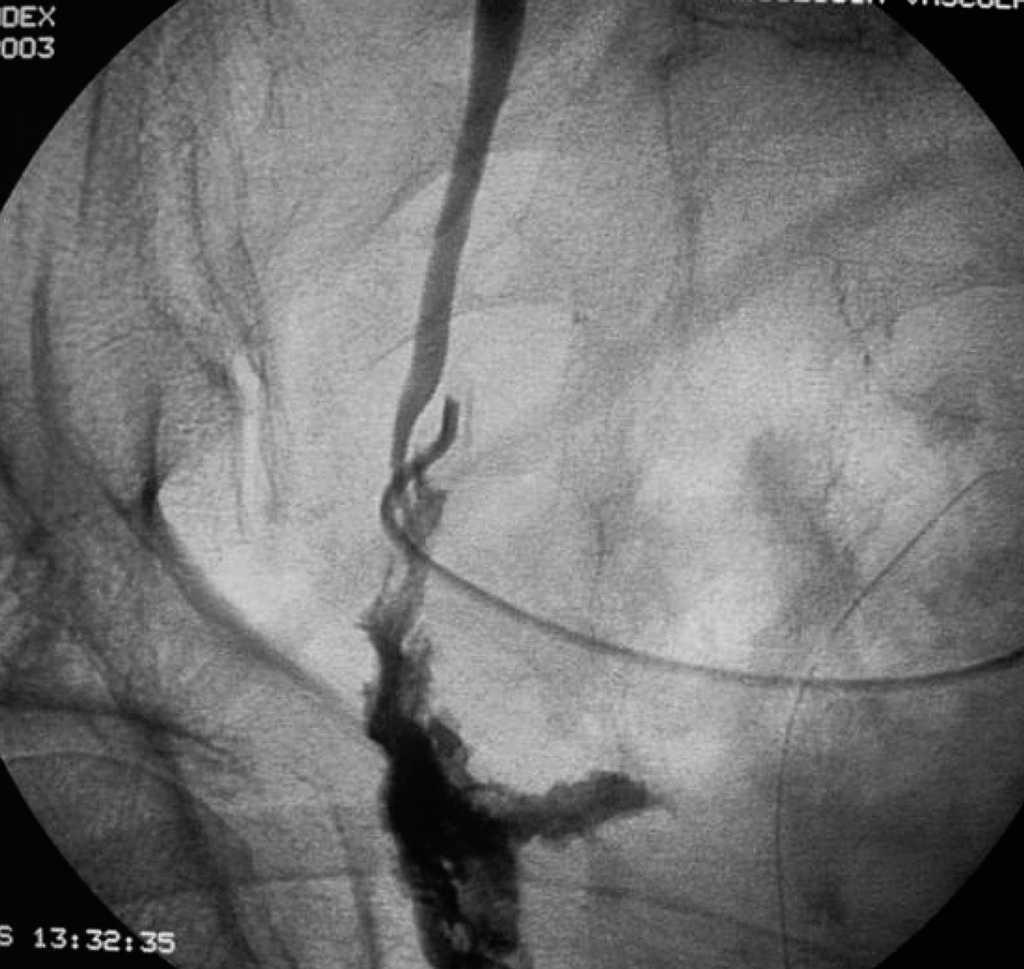

Un paciente precisó de reintervención quirúrgica por lesión del uréter izquierdo detectada en el postoperatorio (fig. 2), y se lo reimplantó por abordaje retroperitoneal. Se trataba de una sección ureteral distal en un caso de RAP y resección por vía perineal de la próstata en un tumor T4. Otro paciente del grupo RAA precisó ingreso por salida de orina por la incisión de Pfannestiel, por una lesión vesical extraperitoneal por el trocar suprapúbico, que se resolvió con sondaje vesical durante 15 días.

Fig. 2. Extravasación de contraste de uréter izquierdo (región distal) por lesión iatrogénica en cirugía del mesorrecto.